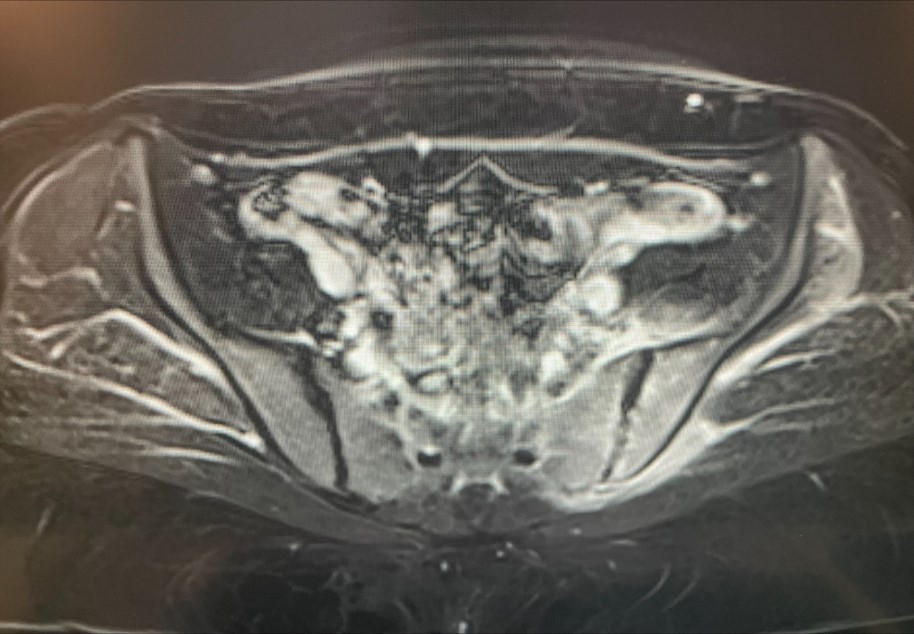

Case Presentation: 24 years old female presented in ER with persistent and progressive pain in the left lower back and left buttock for 1 week. Her pain was sharp, intermittent, severe pain, exacerbated with exertion and relieved with rest. No history of recent trauma or lifting heavy weights.Her past medical history was significant for obesity, and recent chemical abortion using methotrexate 1 month prior to the presentation. Two weeks before the presentation, she was evaluated in the ER for fever, chills, malaise and vaginal discharge. She was noted to have tachycardia and leukocytosis for which she was given intravenous fluids and her tachycardia improved. She was discharged with a prescription of 1 week of cephalexin for presumed endometritis due to recent abortion and an outpatient follow up was scheduled with gynecology. During her follow up, her pelvic exam and pelvic ultrasound were negative for any retained products of conception and she completed her antibiotic without symptom resolution.Physical exam revealed tenderness to palpation in left lower back and left buttock without any neurological compromise in lower extremities. Laboratory studies were significant for erythrocyte sedimentation rate (ESR) of 121 mm/hr and C-reactive protein (CRP) of 11.1 mg/L. Magnetic resonance imaging scan of pelvis was done due to notable elevation of acute phase reactants and it revealed left sacroiliitis with extension into left gluteus minimus.Patient was started on empiric vancomycin and ceftriaxone which was later transitioned to oral amoxicillin-clavulanate and levofloxacin for a total of 6 weeks of antibiotics. Patient had symptomatic improvement and her ESR and CRP trended down on outpatient follow up.